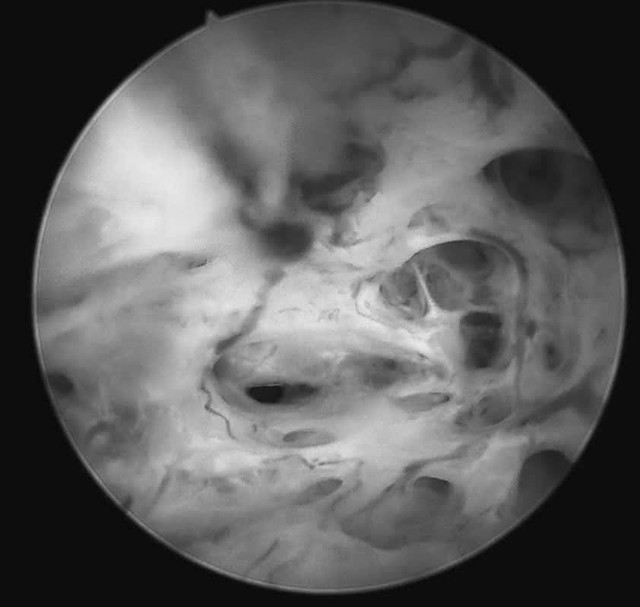

Hình ảnh tổn thương qua nội soi - Ảnh BVCC

Trước tình huống đó, tại Khoa Khám phụ khoa tự nguyện, bệnh nhân được tư vấn thực hiện soi buồng tử cung sinh thiết bằng ống soi nhỏ, một phương pháp cho phép đánh giá trực tiếp buồng tử cung mà không làm tổn thương màng trinh. Ca thủ thuật được ThS.BSCKII Nguyễn Biên Thùy - Trưởng khoa Khám Phụ khoa Tự nguyện trực tiếp thực hiện.

Quá trình soi diễn ra an toàn, nhẹ nhàng. Bệnh nhân hoàn toàn tỉnh táo và có thể quan sát trực tiếp hình ảnh buồng tử cung. Mẫu sinh thiết được lấy ngay trong quá trình soi để làm xét nghiệm mô bệnh học. Kết quả xét nghiệm cho thấy bệnh nhân bị ung thư niêm mạc tử cung.